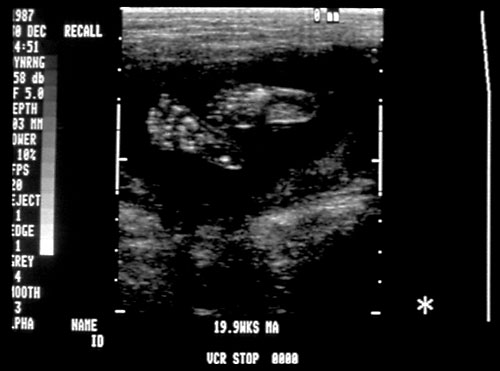

Normal cervical spine at 18 weeks (1). Another normal sagittal view of cervical spine seen in third trimester with folds of fat seen (2). Normal thoracic spine at 18 weeks (3). Normal sagittal view of lumbosacral spine at 18 weeks (4). Normal transverse view of lumbosacral spine at 18 weeks (5). - Extremities (hands/feet)